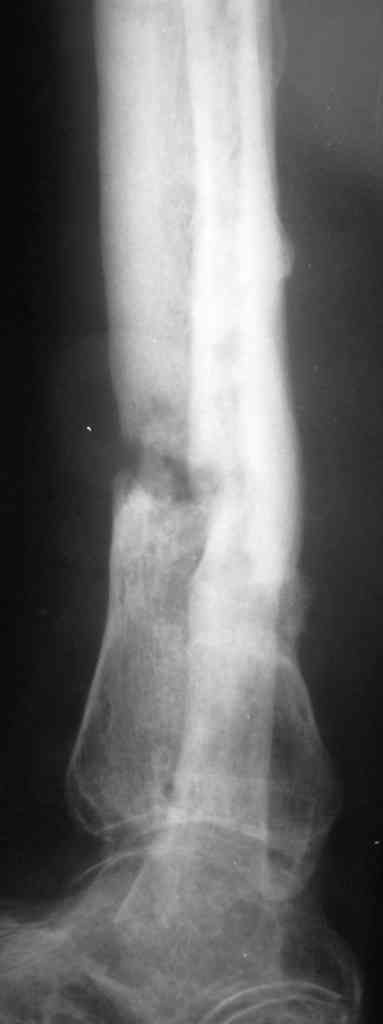

Коротко анамнез: травма в 2004 г. - открытый оскольчатый перелом н/3 голени, имелась рана 4х5 см. по передне-внутренней поверхности. Заживление раны вторичным натяжением. Сращения в АВФ нет. В 2005 г. в нашей клинике произведена костная свободная аутопластика с наложением АВФ. В послеоперационном периоде некроз в области старого рубца 2х3 см., тогда же произведена кожная аутопластика на питающей ножке. Сращения в течение 6 мес. нет, аппарат снят.

В 2006 г. произведена костная аутопластика на сосудистой ножке, иммобилизация гипсовой повязкой. На данный момент признаков консолидации нет.

Периодически у пациента возникают явления дерматита на применение местно лекарственных препаратов на голени, периодически открывается точечный свищ по передней пповерхности в проекции ложного сустава с серозно-гнойным отделянмым.

Укорочение конечности на 4,5-5,0 см., растройств чувствительности нет. При ходьбе конечность нагружает практически полностью при использовании тутора и ортопедической обуви. Внешний вид и R-гр. на фото. У больного еще пока сохранился настрой на лечение.